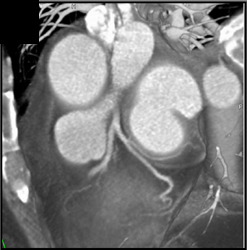

Patent LAD Stent